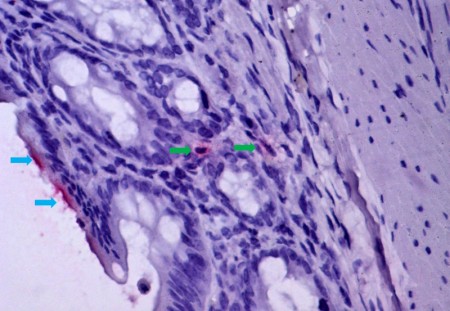

Mucosa intestinal de hámster infectado por el virus de la fiebre amarilla, mostrando isquemia y translocación bacteriana, mecanismo de paso de bacterias y sus productos (marcados en rojo, por inmunohistoquímica) desde el lumen intestinal (flechas azules) hacia la mucosa intestinal (flechas verdes), alcanzando el torrente sanguíneo. El mismo mecanismo de lesión ocurre en humanos con fiebre amarilla fatal (imagen: Amaro Nunes Duarte Neto/HC-FM-USP)

“Inicialmente, estas observaciones fueron tratadas como impresiones anatómicas del patólogo, pero al analizar las láminas constaté lesión vascular en los intestinos y en el estómago, característica de la falta de irrigación. La lesión vascular de la mucosa gastrointestinal permite el paso de bacterias del lumen intestinal hacia la sangre y el hígado, agravando el daño inicial provocado por el virus de la fiebre amarilla y conduciendo a la muerte”, explica Duarte.

Para validar los hallazgos, los investigadores de la USP se asociaron con el profesor Adam Bailey, de la Universidad de Wisconsin-Madison, quien desarrolló un modelo experimental de hámster infectado por el virus. Los análisis de los tejidos animales evidenciaron un cuadro similar al humano, con hemorragias y trombos en la pared intestinal.

“La entrada de bacterias en la sangre de los animales mostró que la translocación es un mecanismo progresivo en la evolución de la fiebre amarilla grave”, afirma Duarte. Los investigadores pretenden ahora analizar muestras de pulmones de pacientes fallecidos para comprender los efectos de esta translocación en el órgano.